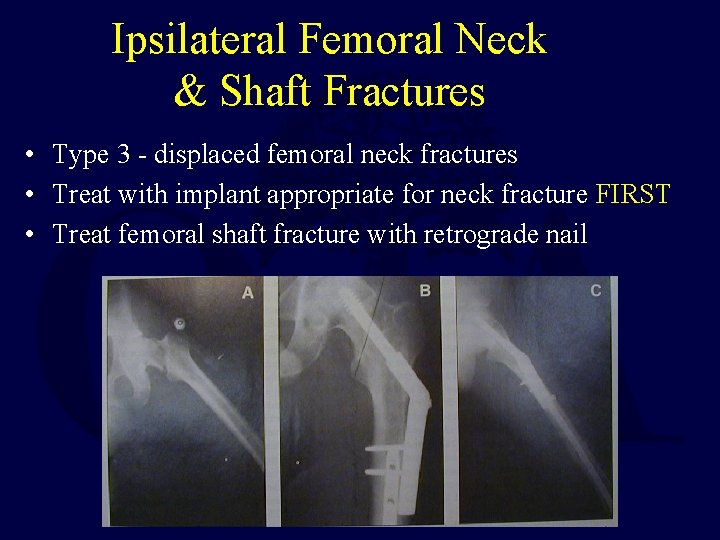

Ipsilateral Femoral Neck & Shaft Fractures • Type 3 - displaced femoral neck fractures • Treat with implant appropriate for neck fracture FIRST • Treat femoral shaft fracture with retrograde nail